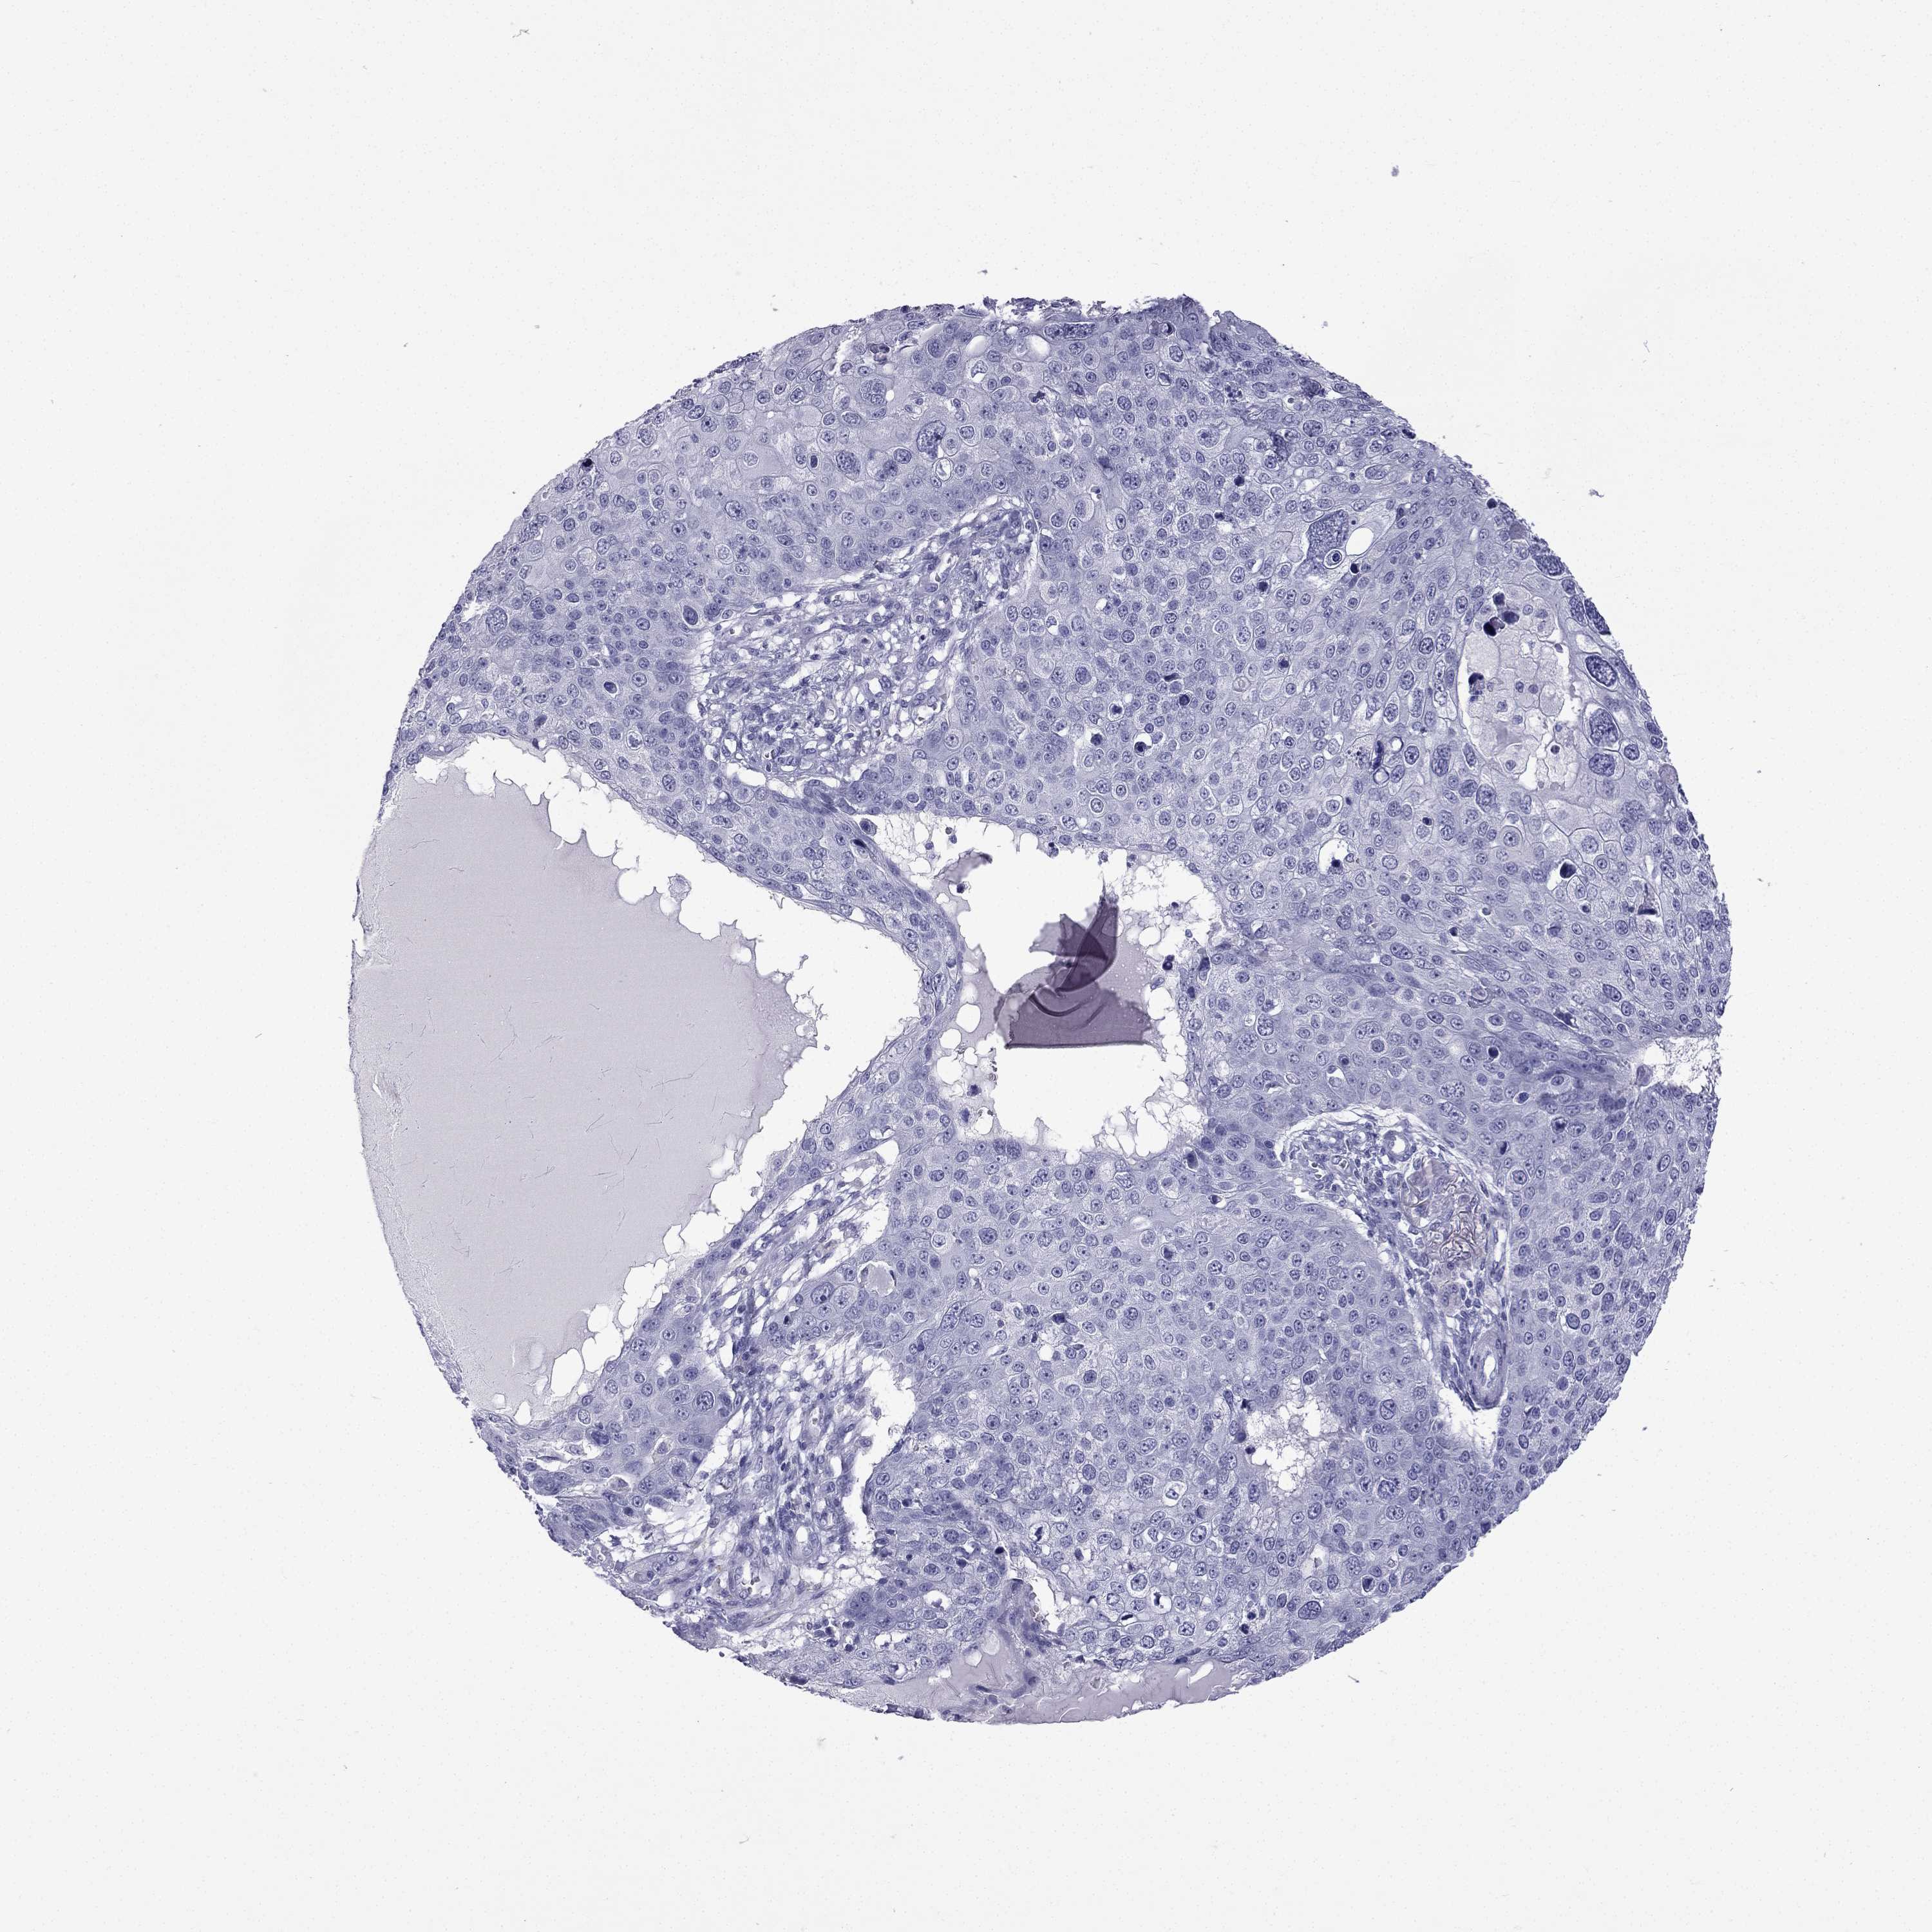

Basal cell and squamous cell cancer

SKIN CANCER - Protein expressioni

A mouse-over function shows sample information and annotation data. Click on an image to view it in a full screen mode. Samples can be filtered based on level of antibody staining by selecting one or several of the following categories: high, medium, low and not detected. The assay and annotation is described here.

Each image is clickable and will lead to virtual microscopy that enables deeper exploration of all samples and also displays staining intensity scores, fraction scores and subcellular localization as well as patient and tissue information for each sample.

Antibody HPA014715

Basal cell carcinoma

Squamous cell carcinoma, NOS